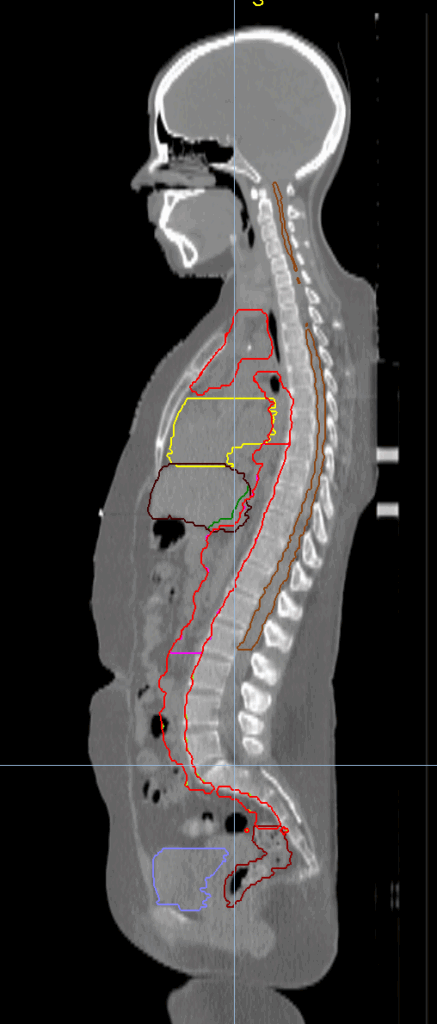

Planning CT Images